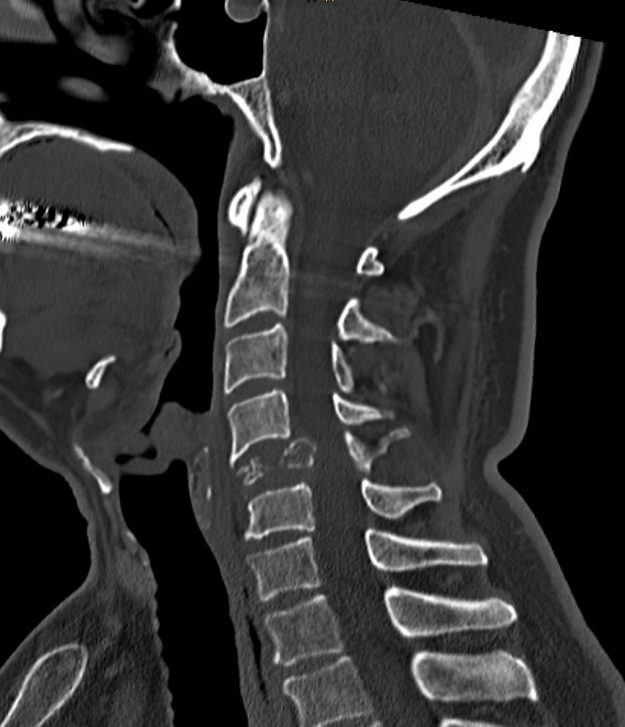

Μετάσταση 10ου Θωρακικού Σπονδύλου (Θ10)

Ασθενής άνδρας 72 ετών με έντονη ραχιαλγία και ιστορικό καρκίνου του πνεύμονα. Ο απεικονιστικός έλεγχος με μαγνητική και αξονική τομογραφία της σπονδυλικής στήλης ανέδειξε μάζα κυρίως στο σώμα του 10ου θωρακικού σπονδύλου (Θ10) με περιβρογχισμό και πίεση επί του νωτιαίου μυελού. (Σημειώστε και τη διήθηση του Θ9 σπονδύλου, χωρίς οστεόλυση). Διενεργήθη αποσυμπίεση του νωτιαίου μυελού…